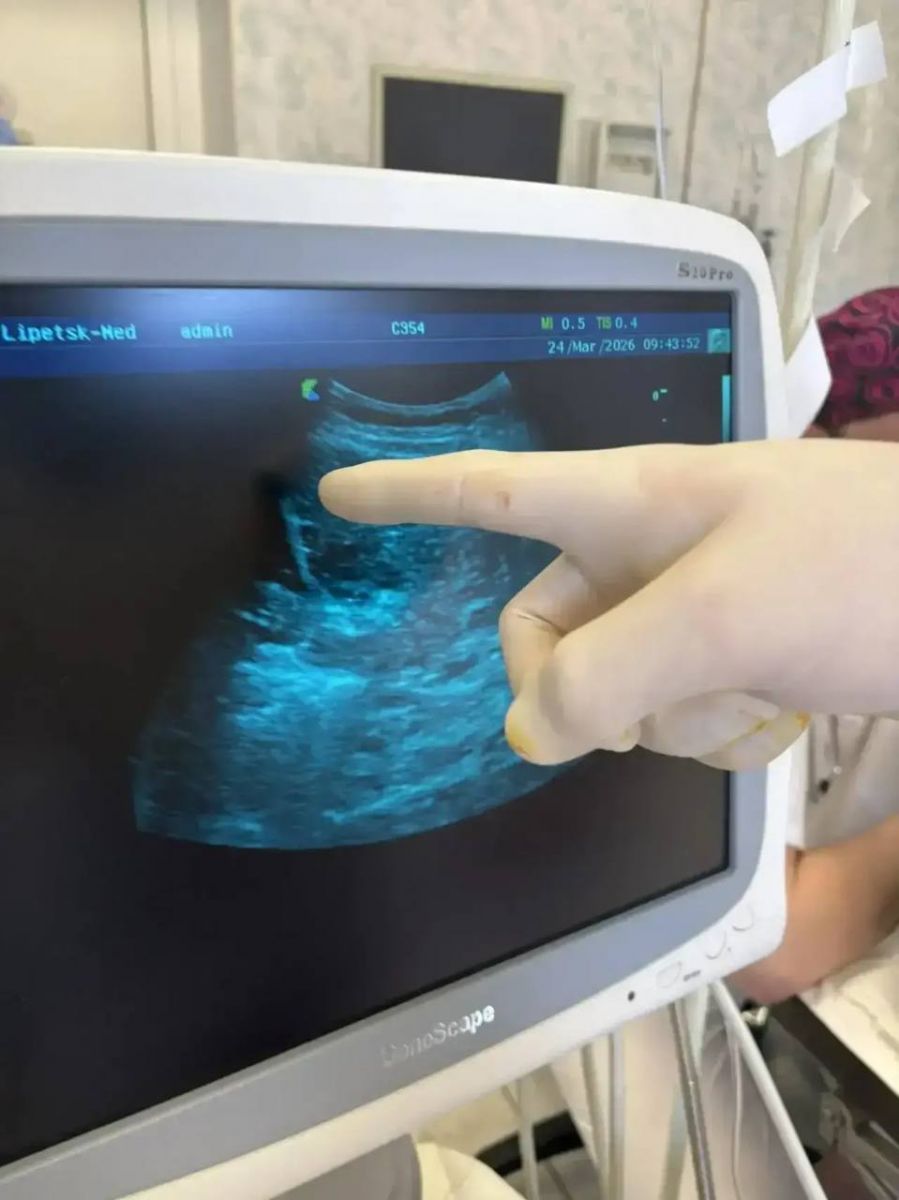

По словам главы ведомства, женщина долгое время страдала от высокой температуры и проходила обследования. Врачи выявили кисту печени с нагноением. Как выяснилось, проблемы начались еще во время коронавируса, но долго не давали о себе знать в полной мере. Со временем состояние резко ухудшилось.

Медики приняли решение о пункционном вмешательстве. В ходе процедуры из печени удалили около полулитра гноя. Операция прошла без осложнений.